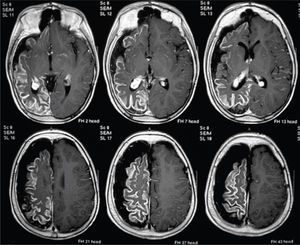

Hallazgos en el EEG pre-operatorioEn adultos se debe buscar una coherencia entre el foco eléctrico y la lesión cerebral mostrada por la RM. Pero en niños esta premisa no es estricta. En niños y adolescentes seleccionados, portadores de grandes lesiones unilaterales en la RM, de tipo congénitas o adquiridas precozmente. A pesar de tener abundantes descargas generalizadas o contralaterales en el EEG, los resultados en el control de crisis son iguales post-cirugía, que los pacientes con lesiones similares y alteración al EEG ipsilateral (32). La expresión difusa del EEG puede deberse a una interacción entre la lesión de instalación precoz y el cerebro en desarrollo (Figura 4).

Niño portador de epilepsia refractaria con crisis de clínica frontal de área motora suplementaria y hemiparesia izquierda. RM de cerebro, corte axial en ponderación T1, con contraste (Gadolinio), muestra un Síndrome de Sturge Weber de hemisferio cerebral derecho. Se ve captación anormal del contraste en toda la corteza hemisférica derecha, así como atrofia de todo el hemisferio. Este caso fue evaluado en el año 2005 en otra institución y “se desechó alternativa quirúrgica por presentar EEG, con actividad ictal contra-lateral”. Post-publicación de Wyllie (Ref. 31) el niño fue evaluado en nuestra institución y pese a persistir los mismo hallazgos, se realizó una hemisferectomía funcional en el año 2011, permaneciendo libre de crisis hasta la fecha.